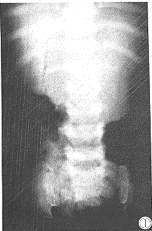

X线检查:脊柱胸腰椎边缘不规则,椎体前方中央突出呈台阶状或变尖,椎管无狭窄,椎弓根间距L5/L1>1(正常),肋骨前、后端见“括号征”(图1,2)。髂骨变短变方,髋臼变浅变平,髋臼顶不规则致密(图3)。四肢长骨粗短,干骺端增宽、不规则致密,并见明显边刺状改变,骨骺小且不规则,骺线狭窄,股骨下端骺核轻微包埋状。双膝双踝关节内翻畸形(图4,5,6)。诊断:假性软骨发育不全。

图1,2 胸腰椎椎体变形,前方中央突出呈台阶状,无椎管狭窄。

肋骨前、后端见“括号征”。

X线改变有一定特征性,且为诊断及鉴别的主要依据[1,3]。其改变有:①四肢管状骨对称性粗短变形,愈向远端愈明显,年龄越大越明显。干骺端增宽、不规整、边缘唇样突出,表面可呈“蕈样”膨凸、“杯口状”陷凹或“波浪状”凸凹不平,松质骨结构粗疏、紊乱,杂以斑点致密影。先期钙化带不规则、骺板狭窄,骨骺变小、不规则、边缘不整和破碎,骨化亦不规则及发生畸形。骨骺出现延迟,但常提前愈合。②脊柱椎体呈“花瓶状”或“台阶状”,椎管无狭窄,椎弓根间距L5/L1>1(正常)。③骨盆发育较小,坐骨大切迹变浅但不如软骨发育不全明显。髋臼缘不规则,髋臼变浅,可有髋内翻畸形。④肋骨前后端可有“括号征”。